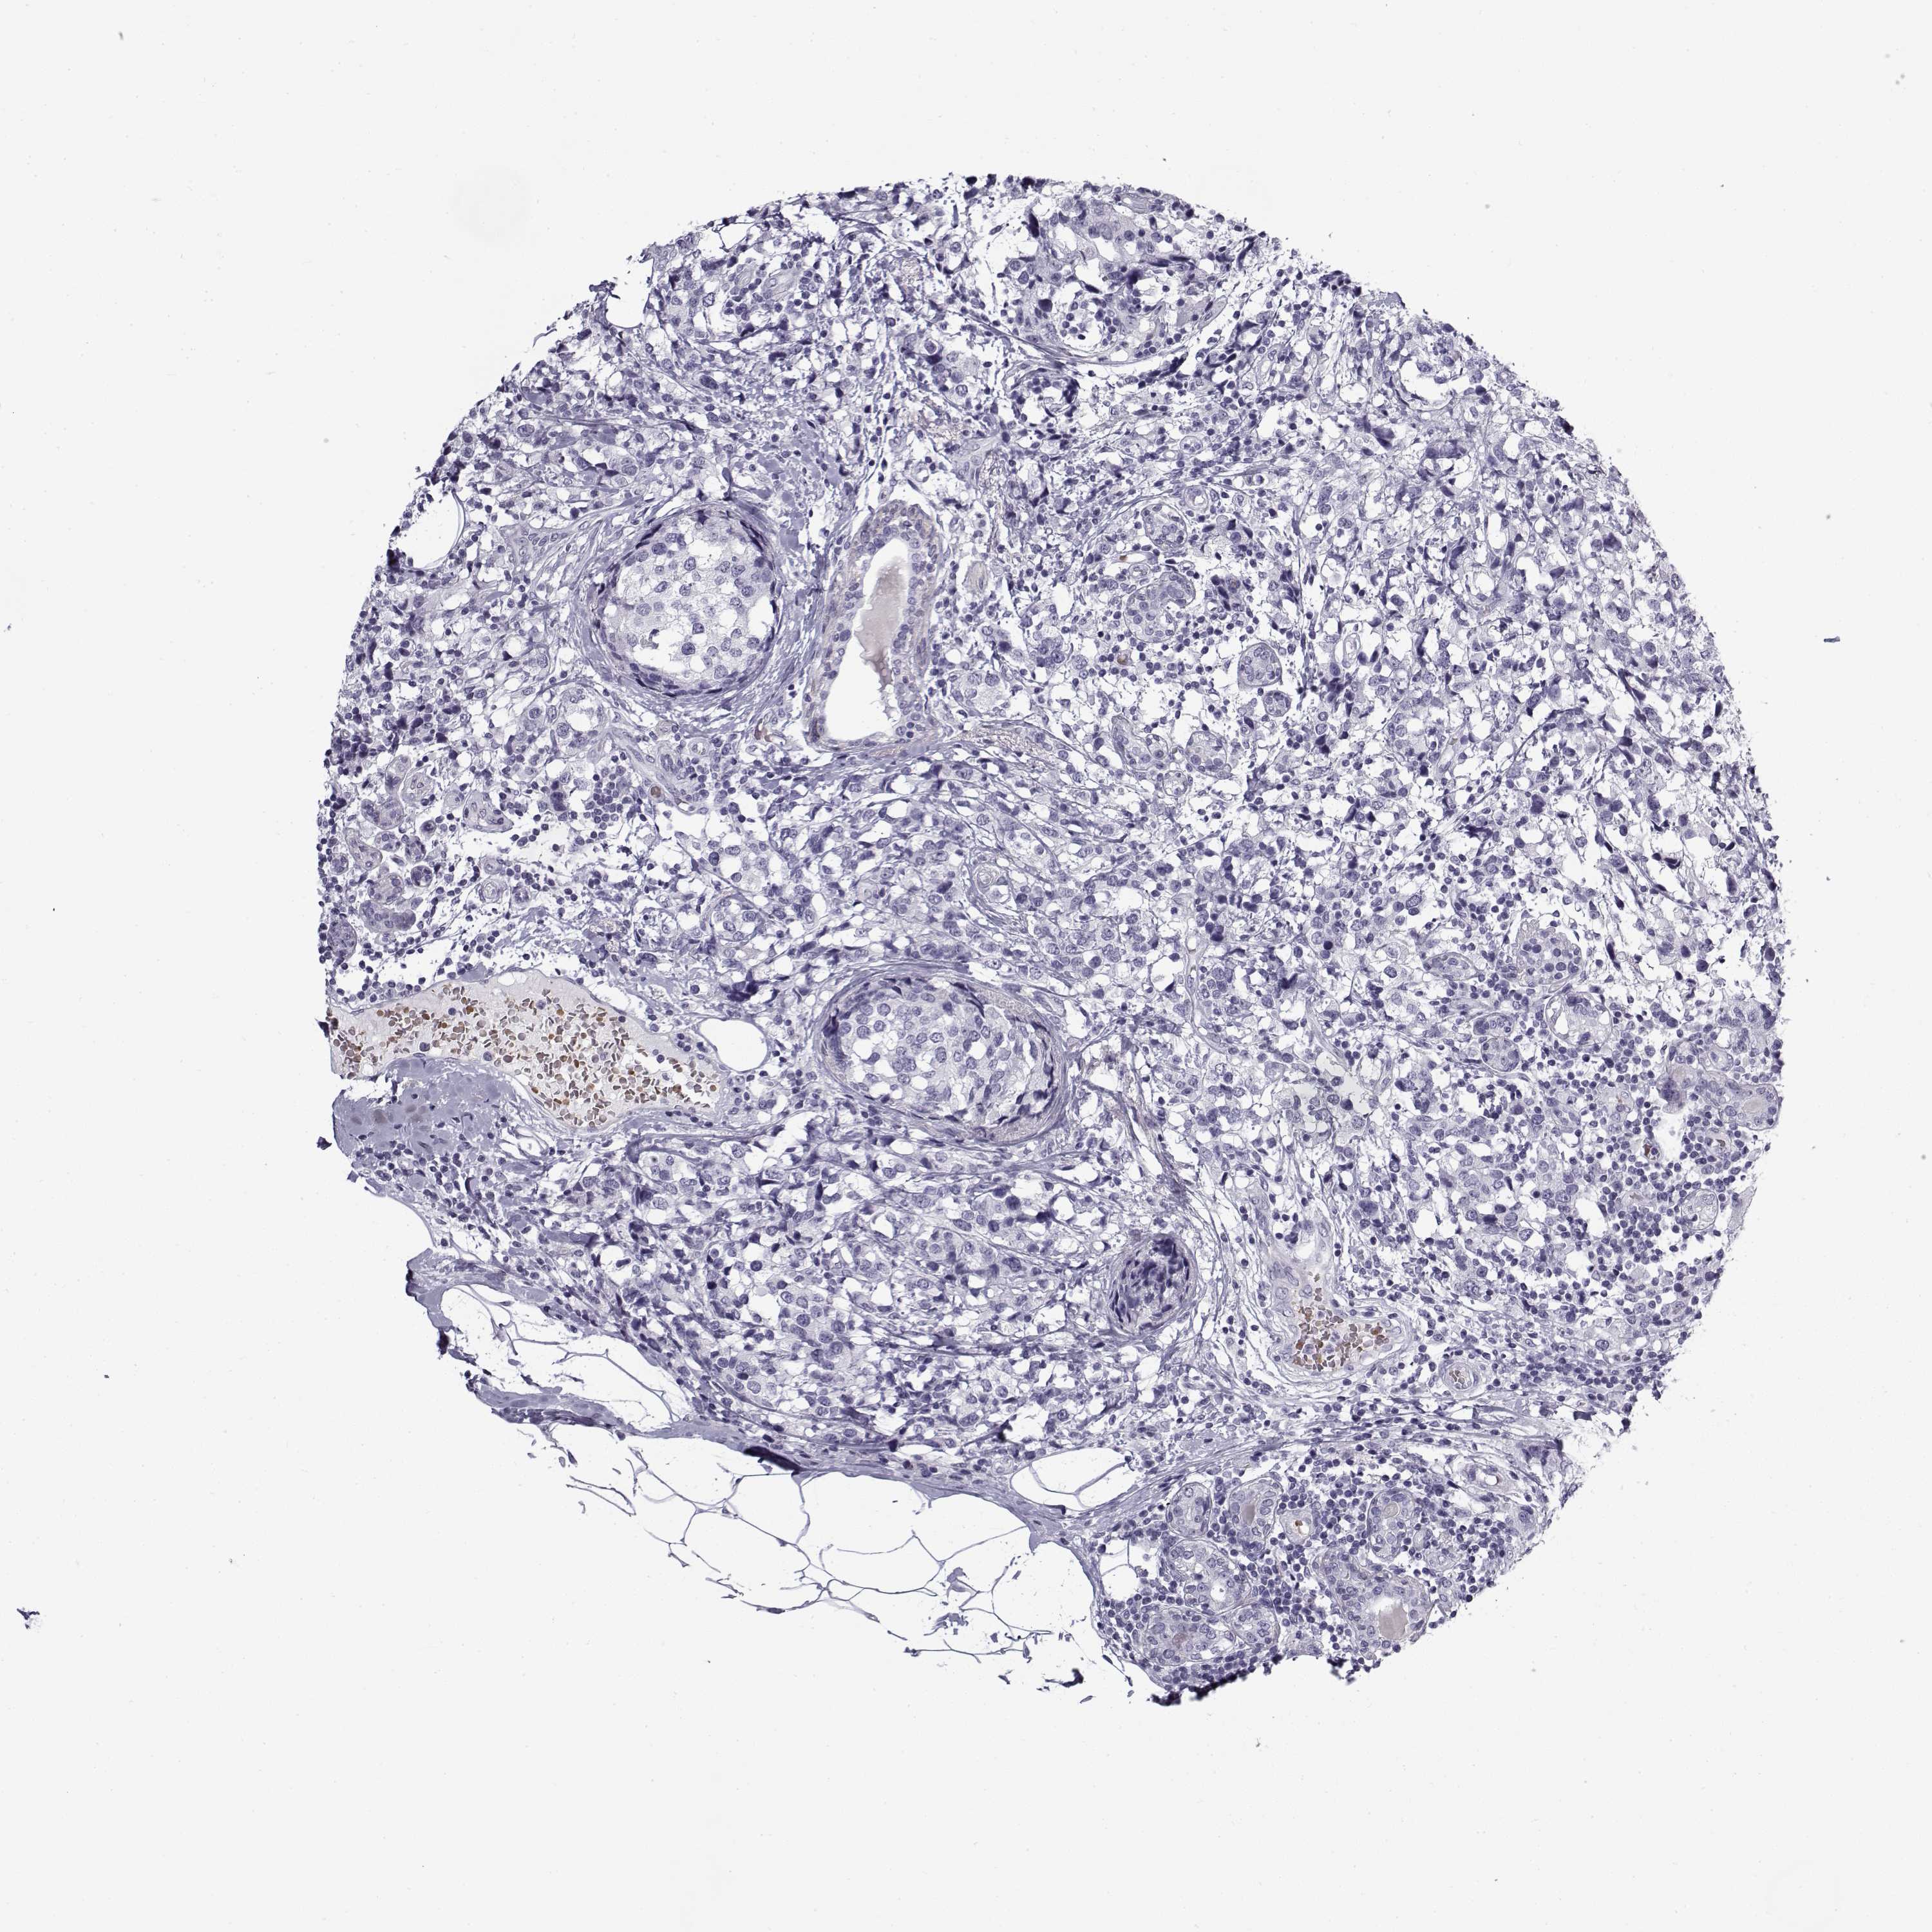

BRCA TCGA BRCA VALIDATION PROTEIN EXPRESSION

Breast cancer

Human cancer